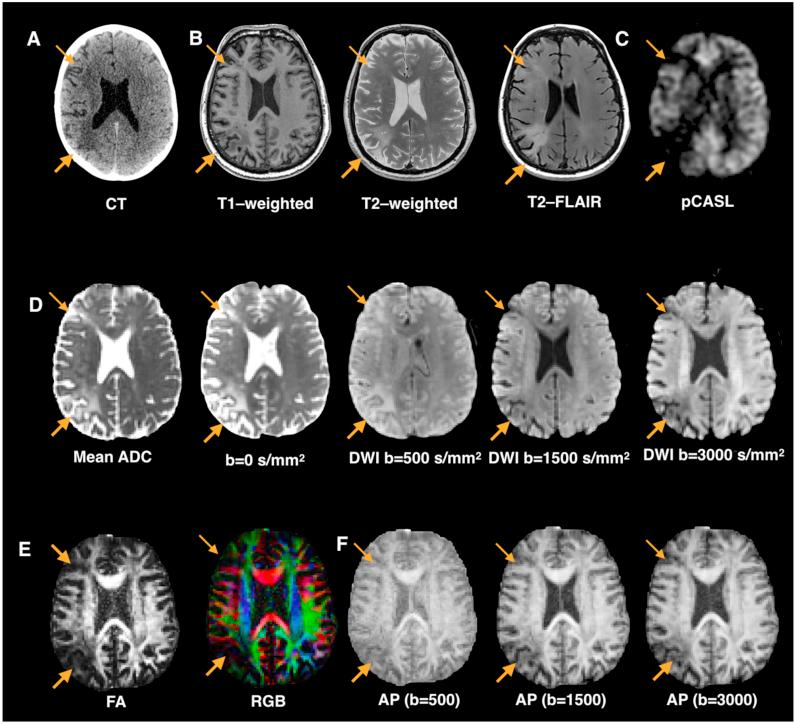

Patients with stroke offer a unique window into understanding human brain function. Mapping stroke lesions poses several challenges due to the complexity of the lesion anatomy and the mechanisms causing local and remote disruption on brain networks. In this prospective longitudinal study, we compare standard and advanced approaches to white matter lesion mapping applied to acute stroke patients with aphasia. Eighteen patients with acute left hemisphere stroke were recruited and scanned within two weeks from symptom onset. Aphasia assessment was performed at baseline and six-month follow-up. Structural and diffusion MRI contrasts indicated an area of maximum overlap in the anterior external/extreme capsule with diffusion images showing a larger overlap extending into posterior perisylvian regions. Anatomical predictors of recovery included damage to ipsilesional tracts (as shown by both structural and diffusion images) and contralesional tracts (as shown by diffusion images only). These findings indicate converging results from structural and diffusion lesion mapping methods but also clear differences between the two approaches in their ability to identify predictors of recovery outside the lesioned regions.